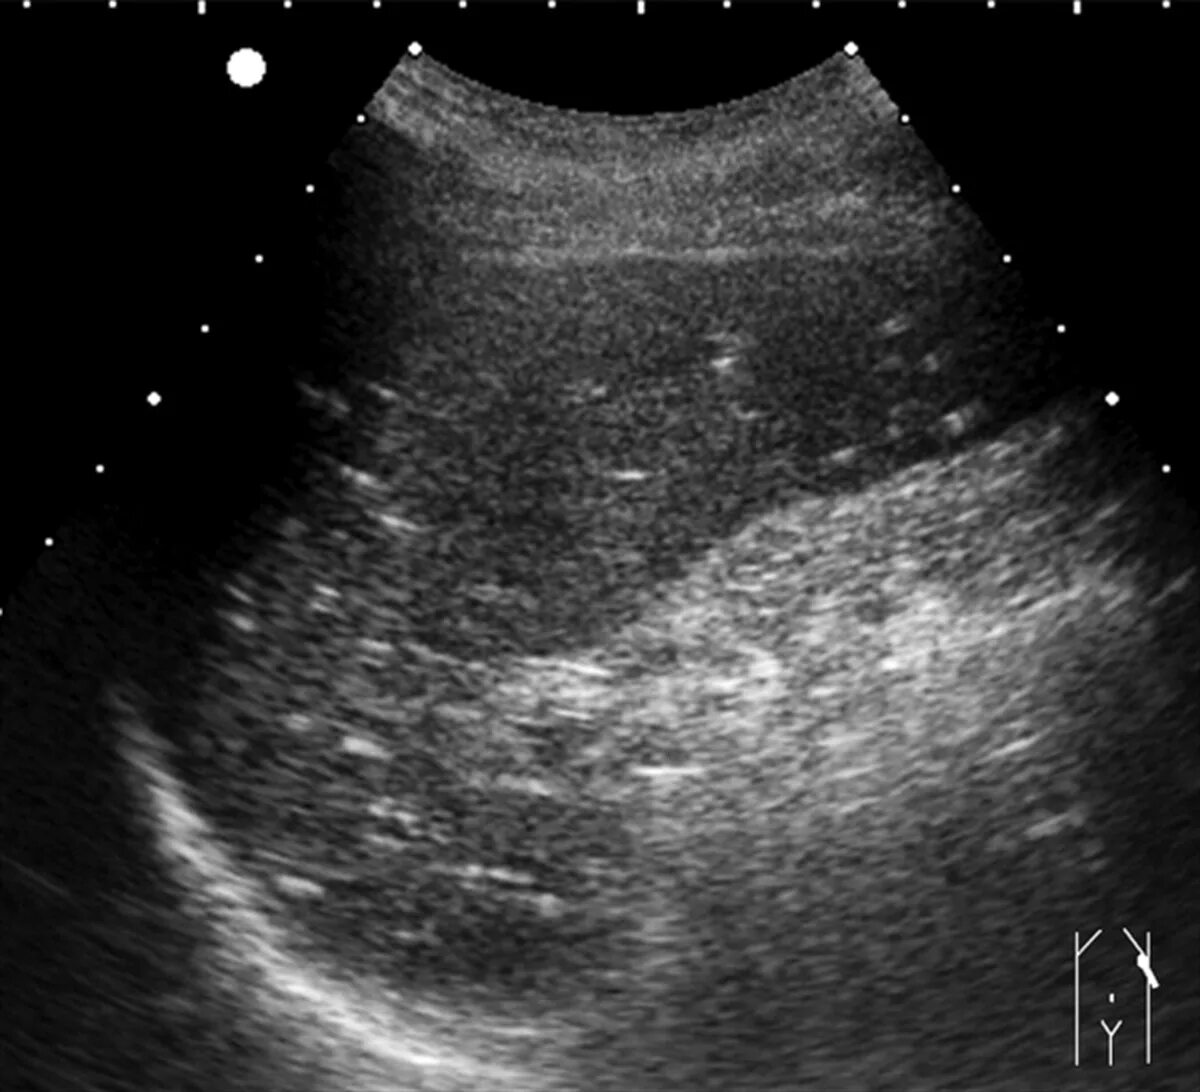

Кальцинат узи